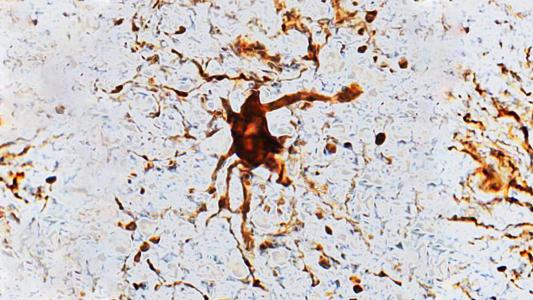

“Zombie” cells grow in the brain after death